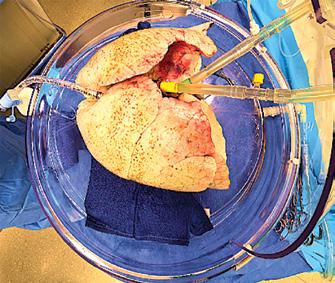

transplantation purposes. It ensures the delivery of oxygen and nutrients to support tissue metabolism and maintains the tone of the microvasculature in the organs while effectively removing toxic metabolic waste. Different temperatures have been explored for ex vivo machine perfusion. These include normothermic machine perfusion at 35–38 °C, sub-normothermic machine perfusion at 20–34 °C, controlled oxygenated rewarming at 8–20 °C, and hypothermic machine perfusion at 0–8 °C. Normothermic machine perfusion maintains the organ at body temperature under physiologic conditions to preserve metabolic activity and viability. (Figure 01)

There are currently three EVLP protocols used globally- Lund protocol, Toronto protocol, and Organ Care System Lung. The original protocol is the Lund Protocol from Sweden which was further adapted into the currently widely used Toronto protocol. The third protocol involves the use of a portable device that effectively reduces the cold ischemic time. Currently, there are four commercially available EVLP devices in the US that use one of the three standard protocols or a hybrid of them. These devices are Lung Assist™ by Organ Assist®, XVIVO Perfusion System (XPS) ™ by XVIVO®(Figure 02), XVIVO LS™ by XVIVO®, and OCS™ by TransMedics®. In collaboration with Traferox Technologies Inc., the Toronto team successfully engineered the second generation of the TorEx Lung Perfusion System. This remarkable advancement specifically targets and resolves the engineering design limitations that were inherent in the original Toronto EVLP system. (Figure 02)

The surgical part of EVLP consists of suturing the left atrial and pulmonary artery cannula (Figure 03), intubating the trachea, and connecting the cannulae to the lines in the XVIVO circuit after dividing and de-airing the tubings.